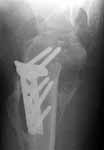

Recently he referred to our physical therapist because of severe limitation of shoulder ROM. The last month he has experienced local pain, increasing with shoulder motions. Also he is disturbed by the prominent implant. Current x-rays attached (images 3,4). The head looks dissolving.

Image 3

The current xrays indicate failure of the implant with loosening. I would make sure there was no evidence of infection ( exam, ESR, CRP etc.) . I would agree with implant removal . I think this would be a suitable case for a circular ring fixator and compression, either a standard IIizarov or Taylor Spatial frame would be appropriate. I note from your previous cases that you have a high level of experience with this method.